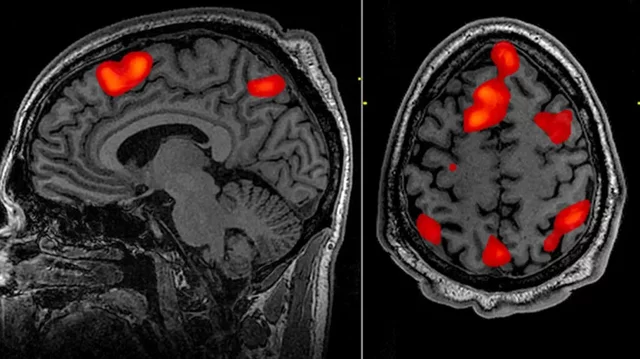

• Neuroimagen

Neuroimagen

Se desarrollan técnicas avanzadas de neuroimagen, como la resonancia magnética funcional (fMRI) y la tomografía por emisión de positrones (PET), que permiten la visualización del cerebro activo durante diferentes tareas y procesos cognitivos.